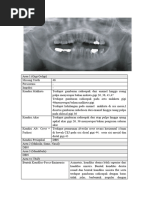

Seorang anak perempuan usia 8 tahun, datang ke dokter gigi ingin merawatkan

gigi 54 berlubang dan tidak pernah sakit. Hasil pemeriksaan klinis diperoleh gigi

52 dan 53 sudah dicabut. Hasil pemeriksaan radiografi diperoleh benih gigi 12

dan 13 lengkap, tetapi masih tertutup tulang alveolar, gigi 54 karies proksimal

(MOD) dengan kedalaman karies media, test vitalitas dingin +, perkusi-, druk-,

perawatan apa yang akan dilakukan pada gigi 54.